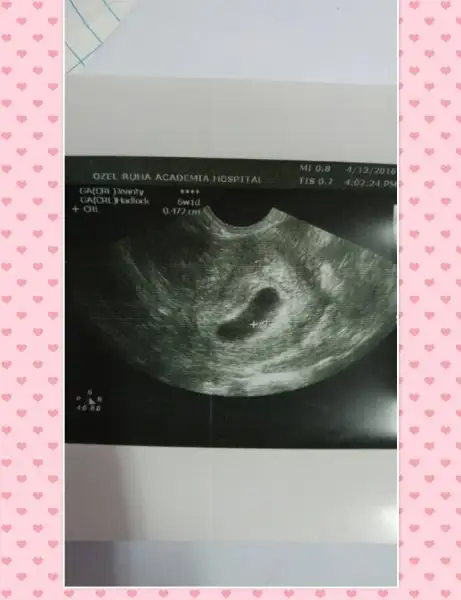

Kızlar burda 7+5 ti yorum yapabilirmisinz :)

Teşekkür ederim cnmUsg karındansa kız gibi,vajinalsa erkek gibi cnm.plasenta sağda,bebekte sağa yaklaşıyor

Simdi gördüm cnm gölge gibi:)usg karındansa erkek gibi,vajinalsa kız gibi.bebekte plasentada solda

Usg karındansa kız gibi,vajinalsa erkek gibi cnm.plasenta sağda,bebekte sağa yaklaşıyor